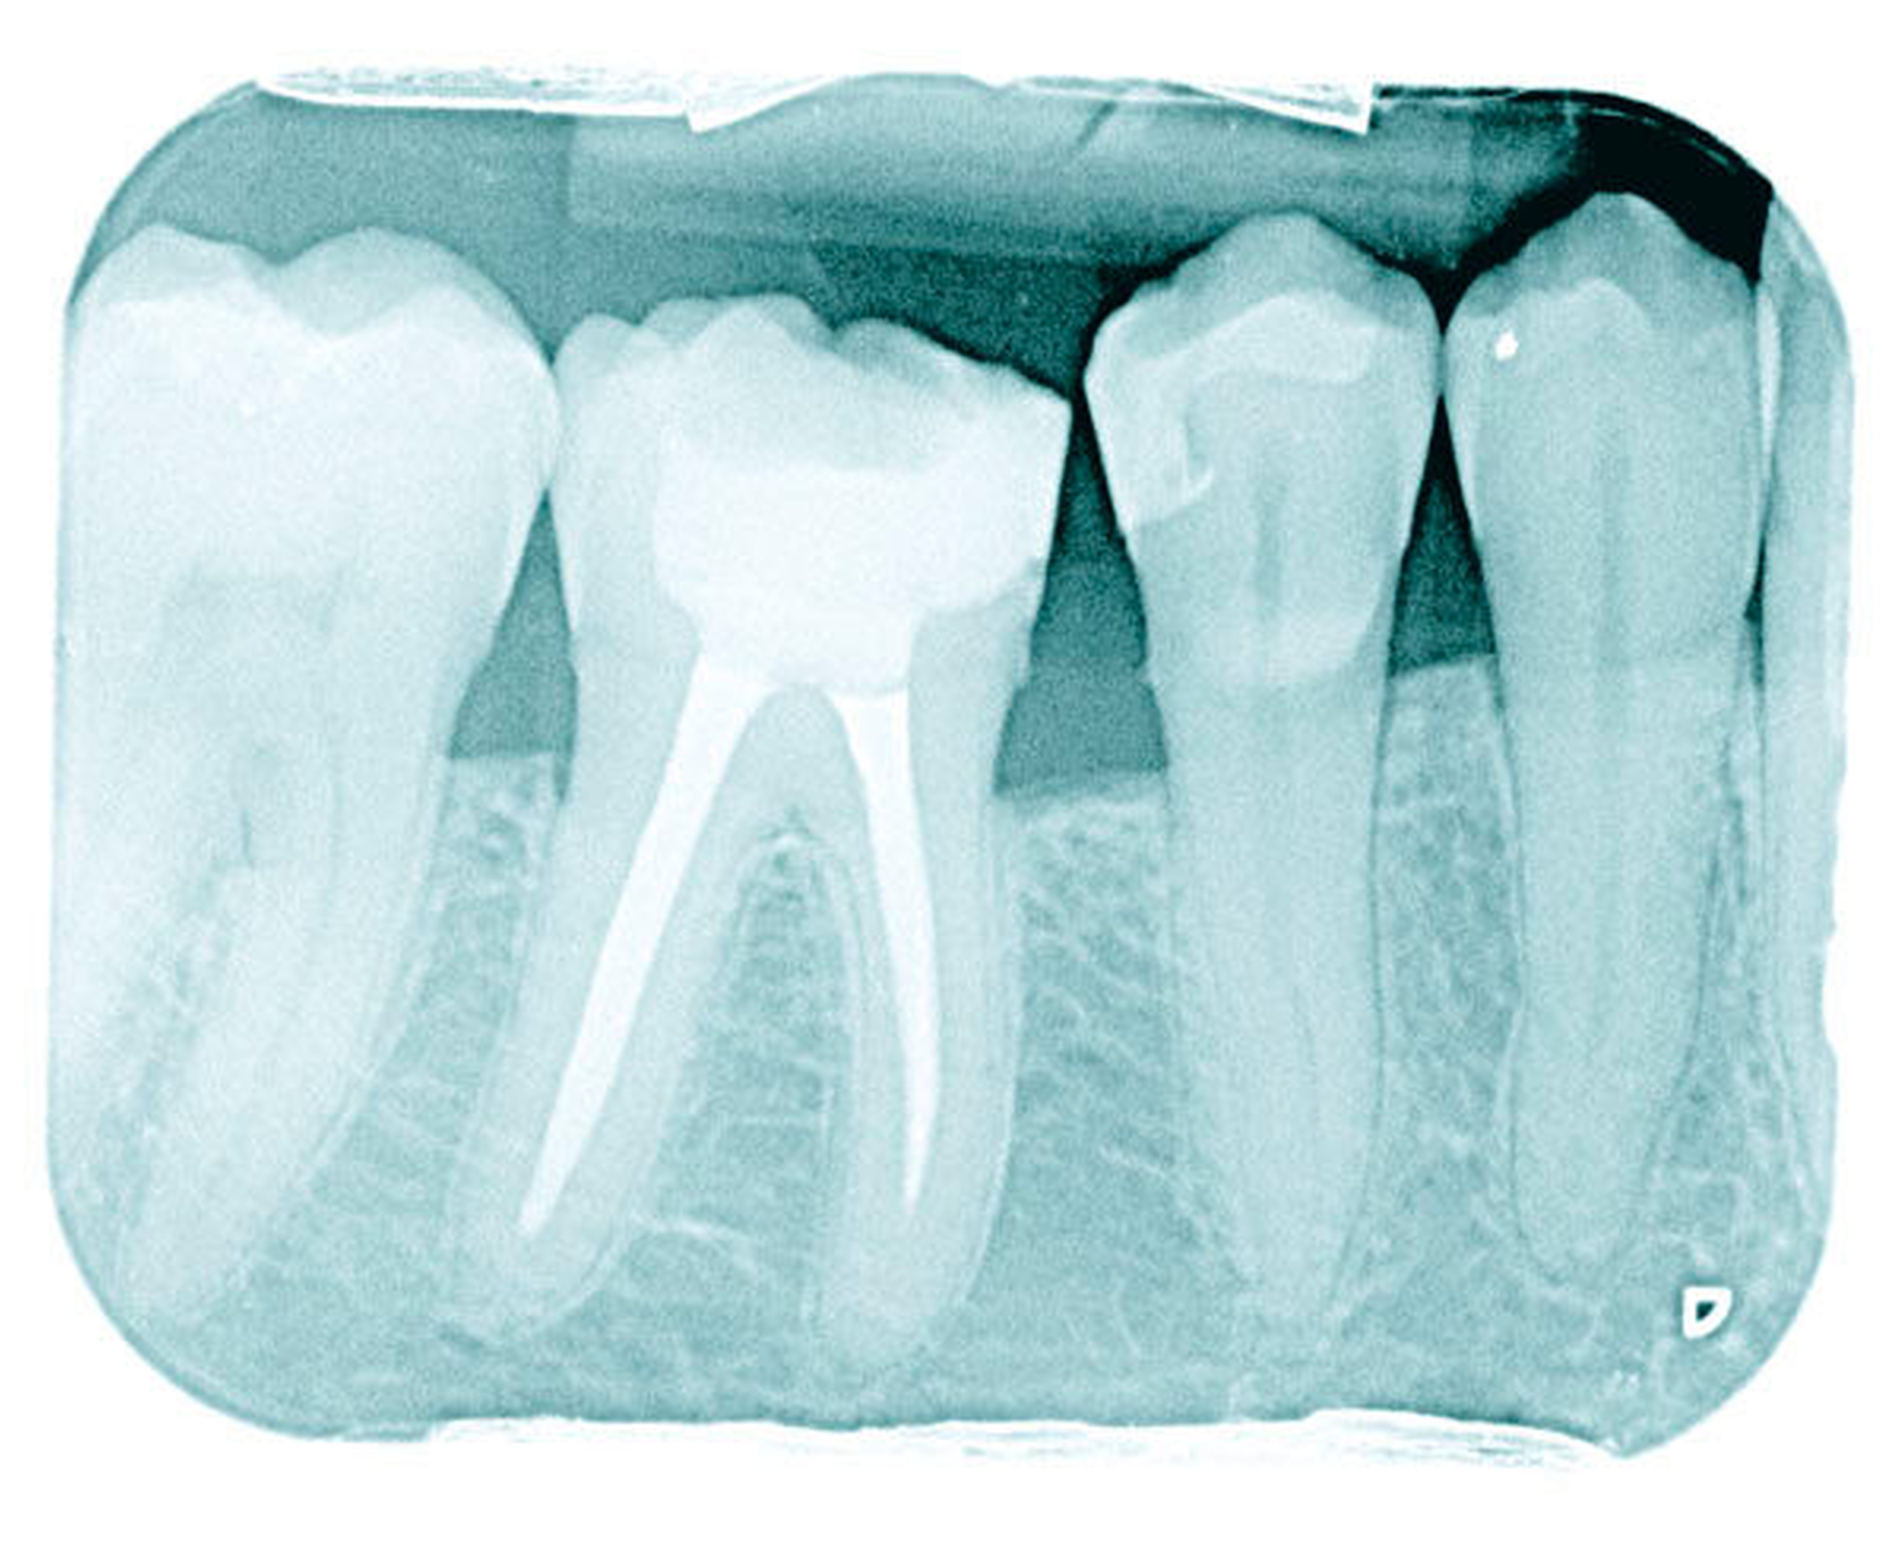

Eine Blutkultur war negativ, er hatte kein Fieber, im Orthopantomogramm fand sich kein Anhalt für Karies. Eine diagnostische CT des Abdomens bestätigte den Abszess, der im Anschluss unter CT-Durchleuchtung drainiert wurde (Abbildung 2). Bei der Punktion des Leberabszesses wurde ein Abstrich entnommen, der reichlich Propionibacteriurm propionicum und Porphyromonas gingivalis (Bacteroides gingivalis) zeigte. Auf eine Antibiotikatherapie mit Metronidazol, später Clindamycin und tägliche Spülungen der Abszesshöhle kam es zu einer raschen Befundbesserung. Nach einer Woche konnte die Drainage entfernt werden. Die Antibiotikatherapie wurde für vier Wochen fortgesetzt. Der Patient war danach beschwerdefrei. Im weiteren Verlauf erfolgte eine Embolisation der pulmonalen arteriovenösen Malformationen.